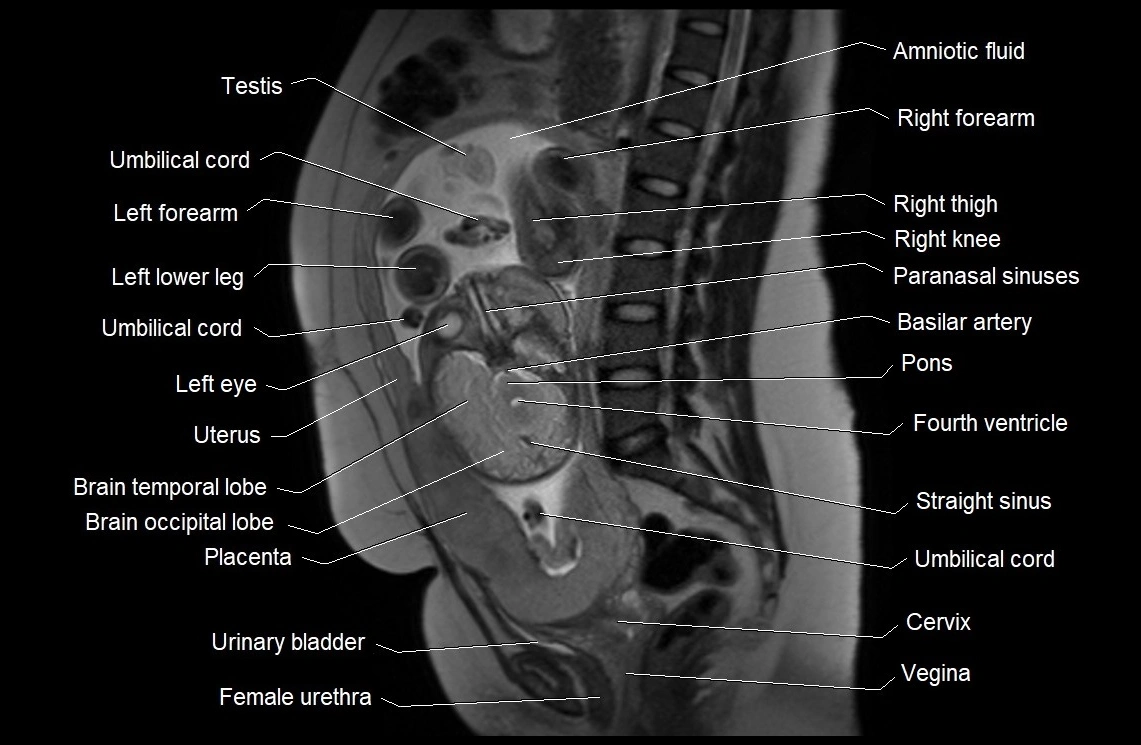

MRI Appearance

T2 HASTE (T2 GRE):

• Amniotic fluid shows very bright hyperintense signal

• Provides natural contrast against fetus and placenta

• Small particles (vernix) may appear as scattered hypointense foci within bright fluid

T1 GRE:

• Amniotic fluid shows low signal intensity (dark)

• Hemorrhage, infection, or proteinaceous content may cause focal or diffuse high signal intensity

MRI image